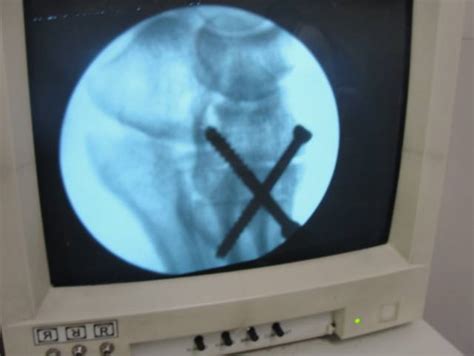

Lateral Condyle Orif

Lateral Condyle Fracture

Lateral Condyle of Femur

Lateral Tibial Condyle Fracture

Pediatric Lateral Condyle Fracture

Fishtail Deformity Lateral Condyle Fracture

Hypoplastic Lateral Femoral Condyle X-rays